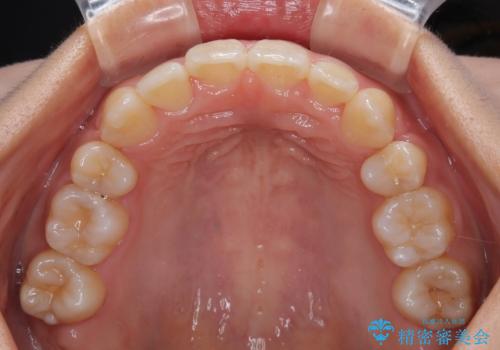

単純に上下左右の第一小臼歯4本を抜歯して口元の突出感を改善することも考えられましたが、上顎骨よりも下顎骨の幅が広いため、より良い咬み合わせを達成することを目的として、急速拡大装置を用いて上顎骨を拡大することとしました。

歯列矯正では基本的に骨格を改善することはできませんが、急速拡大装置(MARPE)を使用することで上顎骨を側方に拡大させることができ、咬合状態を大きく改善することができます。